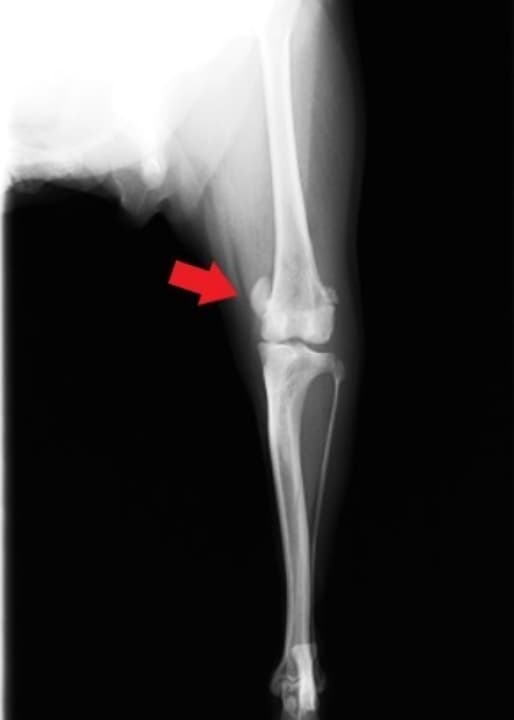

膝蓋骨脱臼とは、膝のお皿(膝蓋骨)が、「滑車溝」という溝から外れて脱臼してしまう病気です。本来あるべき場所に収まってない病気です。

小型犬に多い病気ですが、特に症状を示さないことも多いので、気付かない飼い主さんも多く、驚かれる方もいます。

膝蓋骨が外れると後ろ足をピンと伸ばしたような歩行を行い、数秒で元の歩き方に戻ったりする間欠的な症状が一般的です。

脱臼の程度によってグレード分類(進行度合い)があり、グレードが高くなるにつれ関節や靭帯に傷がついてしまい、痛みがでてきます。

靭帯に傷がついて断裂を起こすこともあります。

さらに病態が進行し悪化すると、筋肉の萎縮や骨、関節の変形が起こり、痛みが増し、内股に歩くなどの歩行障害を引き起こします。

関節の変形が起こる前に手術をすることにより、将来起きるであろう変形や靭帯断裂を防ぐことができます。